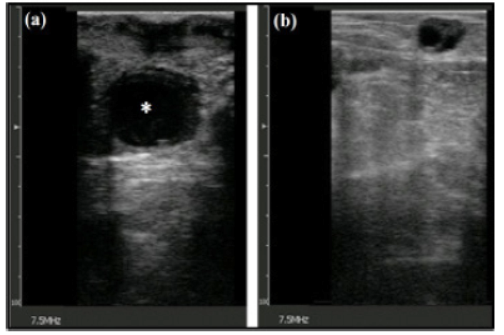

Using ultrasonography to confirm pregnancy in goats 45 days after artificial insemination. A) Pregnant and b) Non-pregnant.